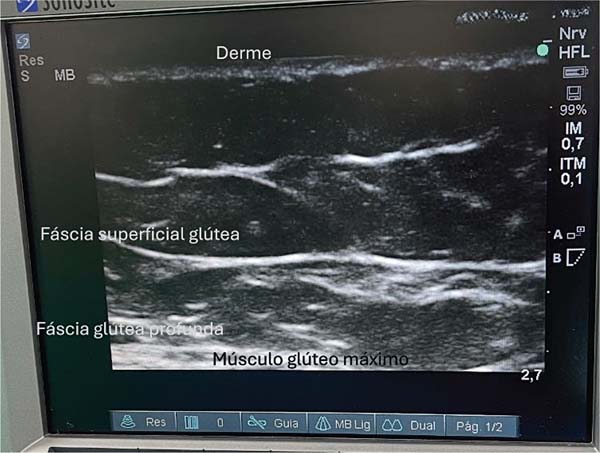

Regional anatomy

Classically, this region features two fascial layers and two fatcontaining subcutaneous tissue layers. The ultrasound evaluation reveals a thinner, more elastic fascial layer, as well as a thicker one. The thinner fascia divides the subcutaneous tissue into two layers, and fat deposition occurs in the space between them (►Fig. 1).

The anatomical structures of the gluteal region are visualized on a tenth-generation iPad (Apple Inc.) using Wi-Fi ultrasound. This examination enables the identification of the following layers: skin, dermis, superficial fat, superficial gluteal fascia (or Scarpa’s fascia), deep fat, and deep gluteal fascia. The latter lies just above the muscle, and it should be avoided at all costs. Ideally, fat grafting occurs in the deep fat layer. Preservation of the deep gluteal fascia, combined with incisions shorter than 1 cm, prevents fat migration into the muscle plane.9,10